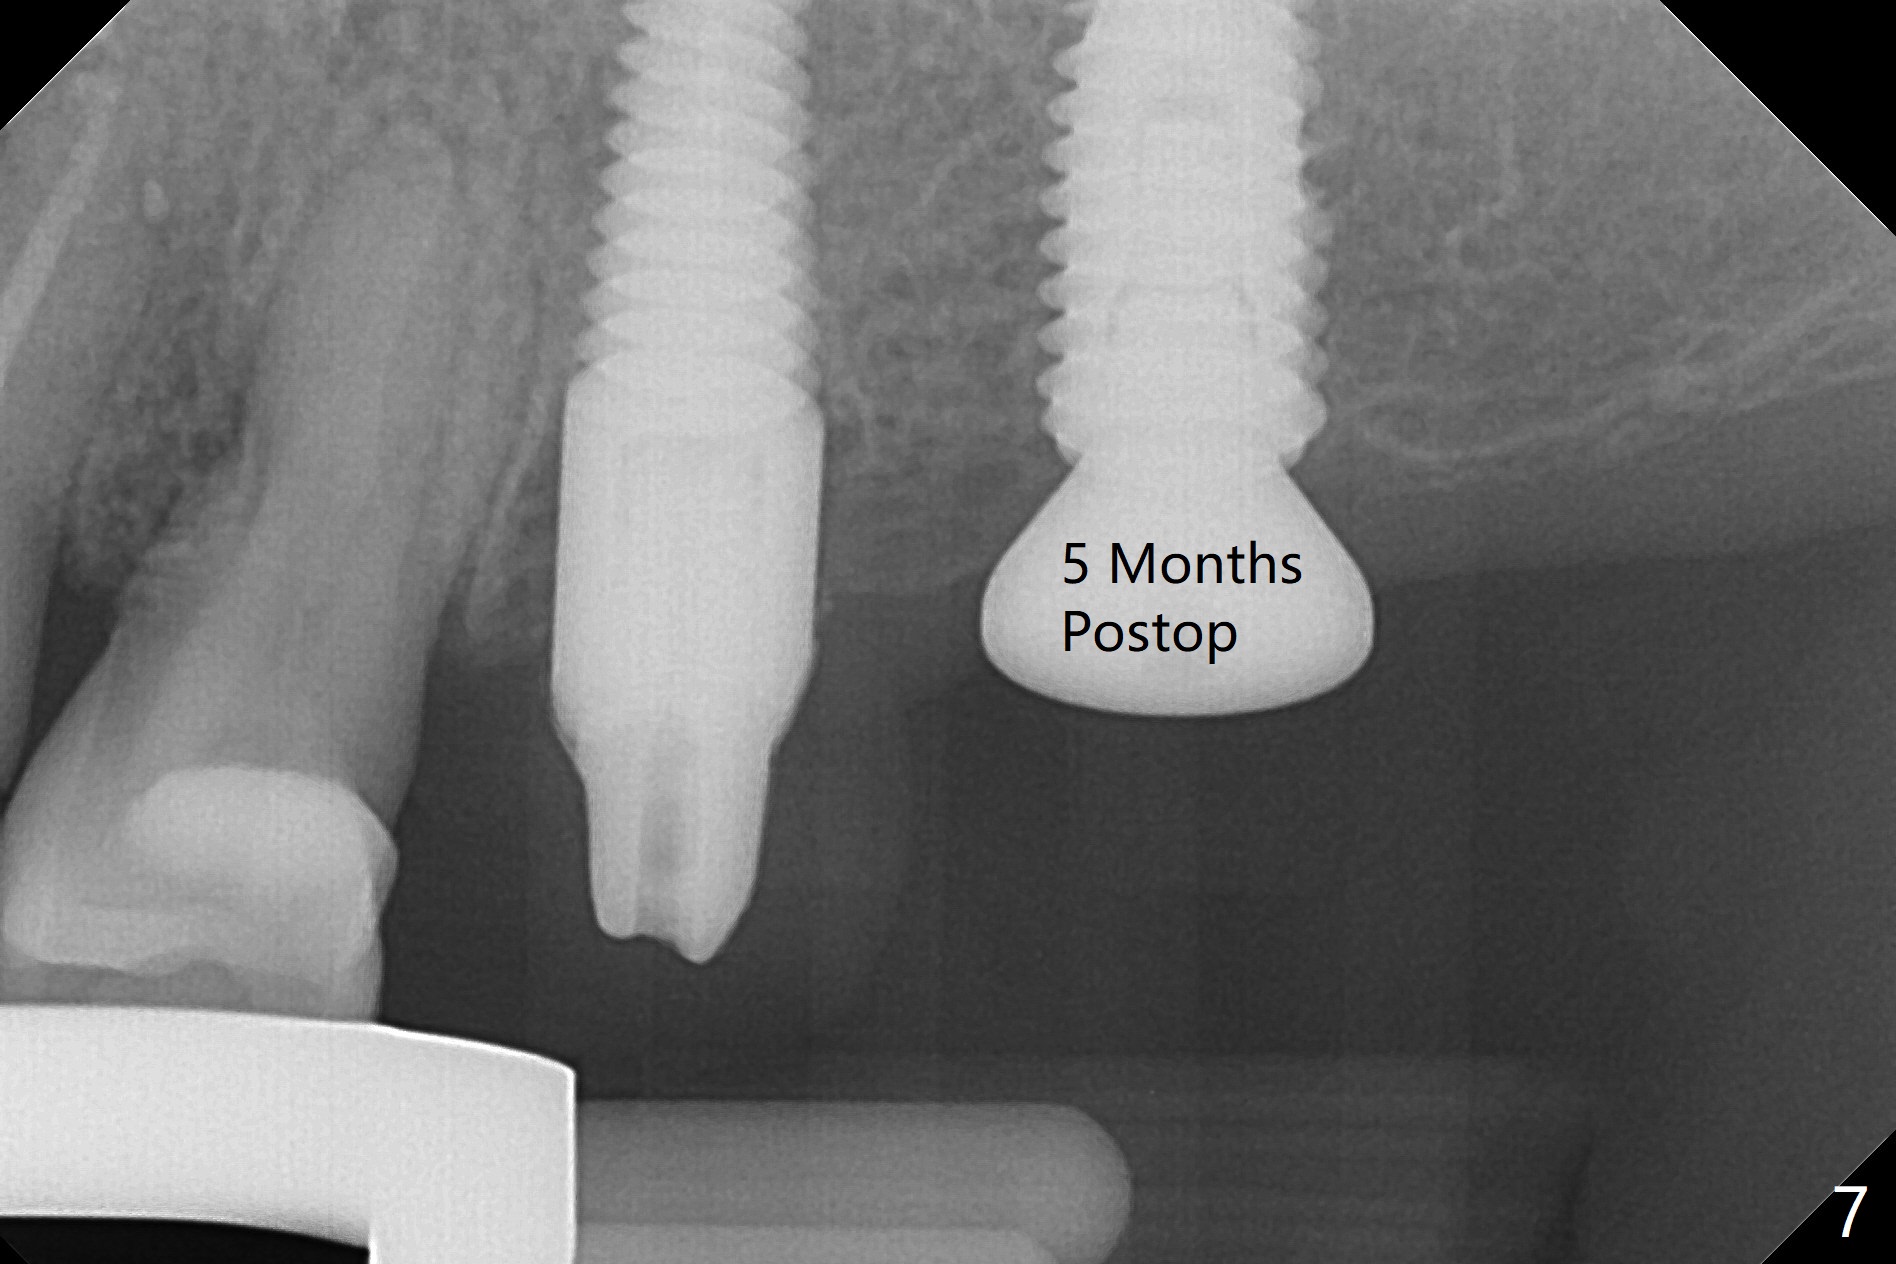

M

As a surgeon, I have never felt that my scalpel is as precise as media claims to be until guided surgery is introduced. The implants at #14 and 19 are placed as precisely as planned as well as painlessly and quickly (Fig.1-4). What else can we ask for? The gingiva around the healing abutment (5.5x3 mm) at #19 is erythematous (Fig.5). Later a longer healing abutment is used (Fig.6 (5.5x5 mm)). There is no bone loss 5 months or 7 months postop (Fig.6-9). The abutment screw is loose 3 months post cementation due to unfavorable crown/implant ratio (Fig.10); in fact the abutment is incompletely seated. Bicon implants will be in consideration to reduce screw loosening if implants are to be placed at #15 and 18. The abutment screw at #14 becomes loose 10 months post cementation; after retorque at #30 Ncm, the abutment is incompletely seated (Fig.11). It remains the same after use of 4.6 and 5.6 mm profile drills (Fig.12). A healing abutment is placed. When the patient returns, use planning kit and try to place a 5.2x5.5(2) cemented abutment. In fact it works (Fig.13). The crown at #19 is loose again 1 year 5 months post retightening. After removing crown/abutment, the mesial surface of the crown is heavily reduced. The crown/abutment is reseated to make sure that there is no proximal contact between the neighboring teeth (Fig.14 arrow). Because of tilt of the PA, it is difficult to tell the tightness of the contact between the implant and abutment, but the apical space is significantly reduced (*, as compared to Fig.10). Pick up impression is taken for porcelain addition occlusomesially. Two months later the patient returns for crown recementation. When the abutment is reseated with the repaired crown, the seating is incomplete (Fig.15). The abutment is completely seated when it is turned free hand with the flat surface of the abutment faces distal (Fig.16 D). The screw is torqued 20 Ncm before reimpression.